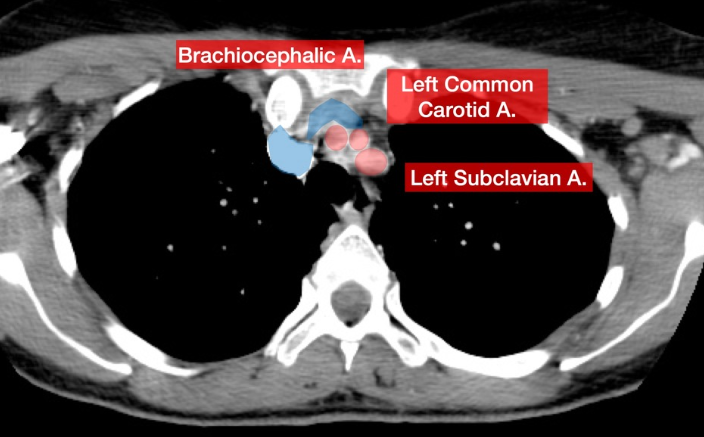

Bifurcations from the Aortic Arch

Brachiocephalic (RT)

RT subclavian → RT vertebral

RT common carotid → RT ICA and ECA

LT common carotid → LT ICA and ECA

LT subclavian → LT vertebral